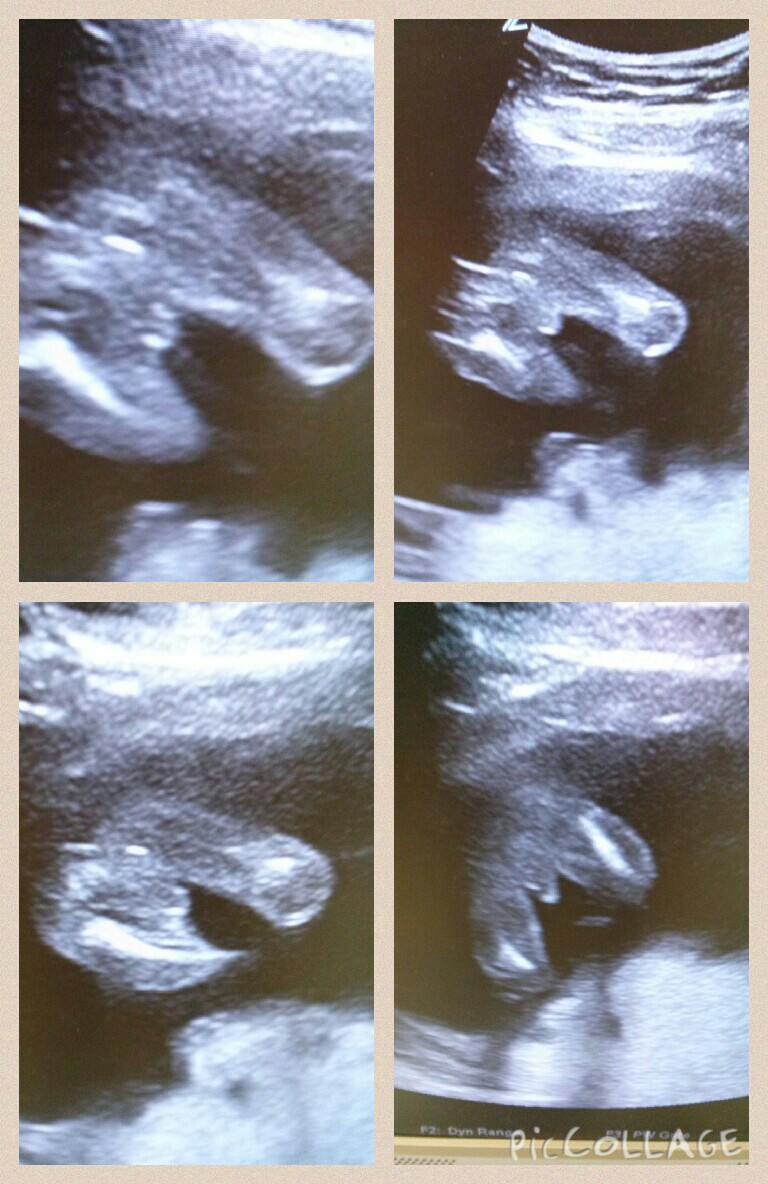

This was done at 18 weeks 1 day BUT not by a technologist....so need a techs opinion Are those boy parts? Thanks for looking!

It's a boy.